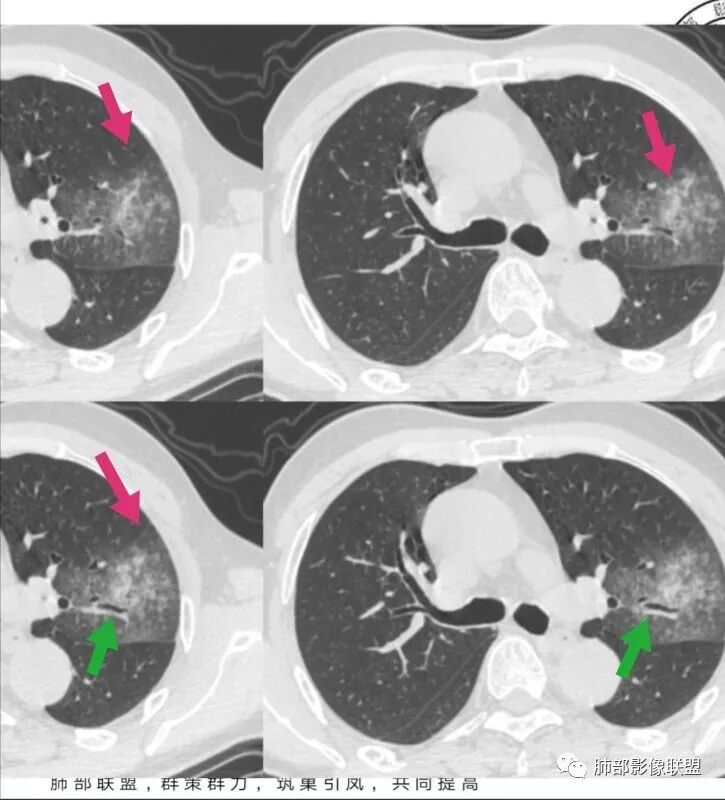

我标示一下,尖后段搭到一部分,前段也占了一点点。

主体在舌段

有占位效应吗?

有,斜裂局部膨隆

边缘膨隆,叶间裂有局部膨出下坠

有膨隆+收缩

密度?

实变为主,加周围模糊GGO

GGO+实变

南边:

强化如何?

强化有疑问,前面感觉有低密度的,有些图好像又均匀

不均匀中度强化

不均匀轻中度渐进强化。

整体形态

切面所致,要看长轴

外围大,内带小

支气管?

支气管外面堵了,近端有扩张

有堵塞,有狭窄

中远端堵塞,堵塞端圆钝

炎性? 肺炎型肺癌待排

血管受侵了吧

空洞内侧软组织肿块,比较支持恶性吧

这个空洞的性质很重要,对最后诊断结果影响大,如果中间没有曲菌球,那就是偏心空洞,指向恶性,如果是曲菌球引起的新月形改变,那就不一定。至于到底是曲菌球还是偏心空洞,需要仔细看看强化情况。